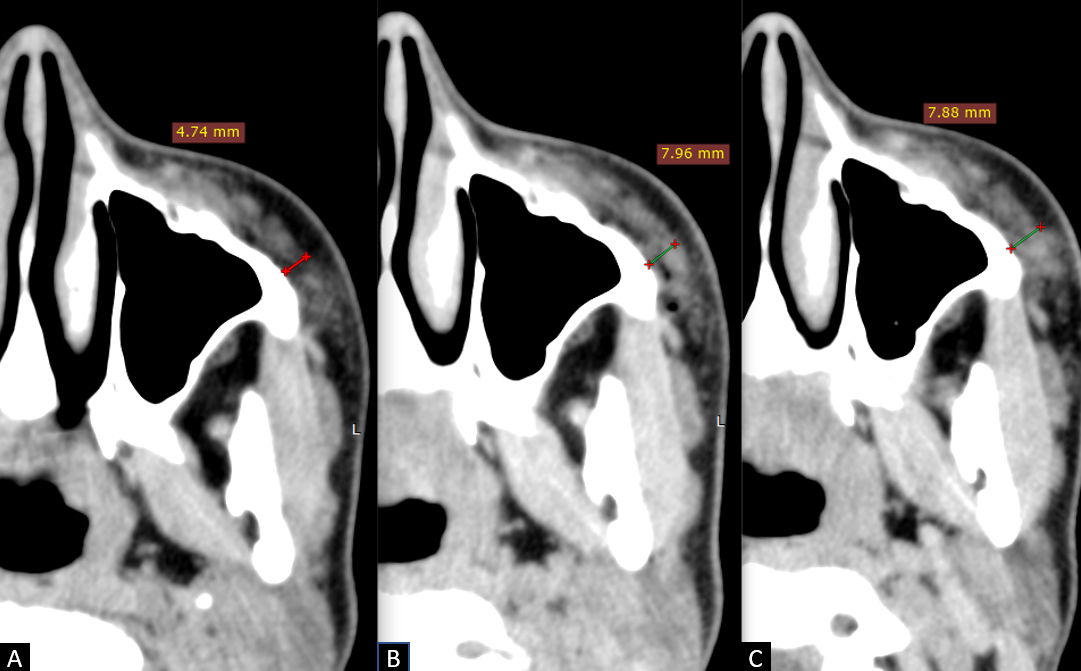

Данные МСКТ: на сагиттальных срезах подбородочной области (рис. 9) определяется имплантат, интимно прилежащий к подбородочному отделу нижней челюсти сзади и к подбородочной мышце спереди, в виде включений плотностью аналогичной плотности мышечной ткани. В динамике отмечается увеличение толщины филлера с 4,8 мм до 7,4 мм, миграции и признаков инкапсулирования препарата не выявлено.

Рис. 9

МСКТ сканы подбородочной области, сагиттальная проекция

А – до инъецирования, толщина имплантата 4,8 мм

В – сразу после инъецирования, толщина имплантата 7,4 мм

С – через 3 недели, толщина имплантата 7,4 мм